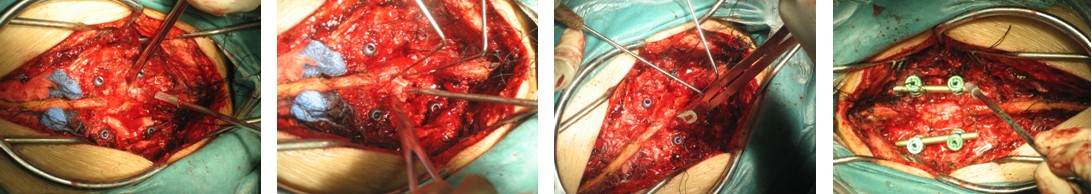

4. 典型病例:病例1,患者男性,40岁,司机。主因胸腰背部疼痛3年,肛周麻木、性功能减退并伴双足下垂2年,症状加重且二便肥力、无法工作1年入院。入院查体:一般情况良好,体胖、体重105kg。步态不稳,步行缓慢。胸腰段脊柱背部轻压痛,无放射。双侧股四头肌力IV级,双侧胫前肌力I级,双侧足下垂。鞍区感觉减退,无病理征。双侧跟、膝腱反射消失。血化验检查正常。X线平片显示T12~L1椎间隙明显变窄。CT显示T12~L1椎间盘突出并椎体后缘离断。MRI显示T12~L1椎间盘呈中央型突出,椎管狭窄,脊髓明显受压变形。入院诊断:T12~L1椎间盘突出症伴椎体后缘离断,马尾神经损害。术前检查完成后,在气管插管全麻下行上述经极外侧入路T12~L1椎间盘切除手术治疗,整个手术过程顺利,无术中及术后并发症发生,术后1周顺利出院。出院时,其双侧股四头肌、胫前肌肌力已分别恢复至V级和III级;鞍区感觉减退亦有明显好转。术后显示T12~L1突出之椎间盘及离断之椎体后缘已被完全切除,椎间融合器及椎弓根螺钉位置佳,脊柱局部生理曲度良好(图2a~2l)。病例2,女性患者,59岁。主因间歇性跛行,双下肢无力3年入院。入院诊断:T11椎体后上缘骨软骨瘤。以与病例1相同的术式行椎体骨软骨瘤的彻底切除(图3a~3l),无手术并发症发生,术后患者下肢症状明显改善。

图2e~2h. 典型病例1手术中情况: 关节突关节切除, 椎间盘切除, 椎间融合器植入及椎弓根固定